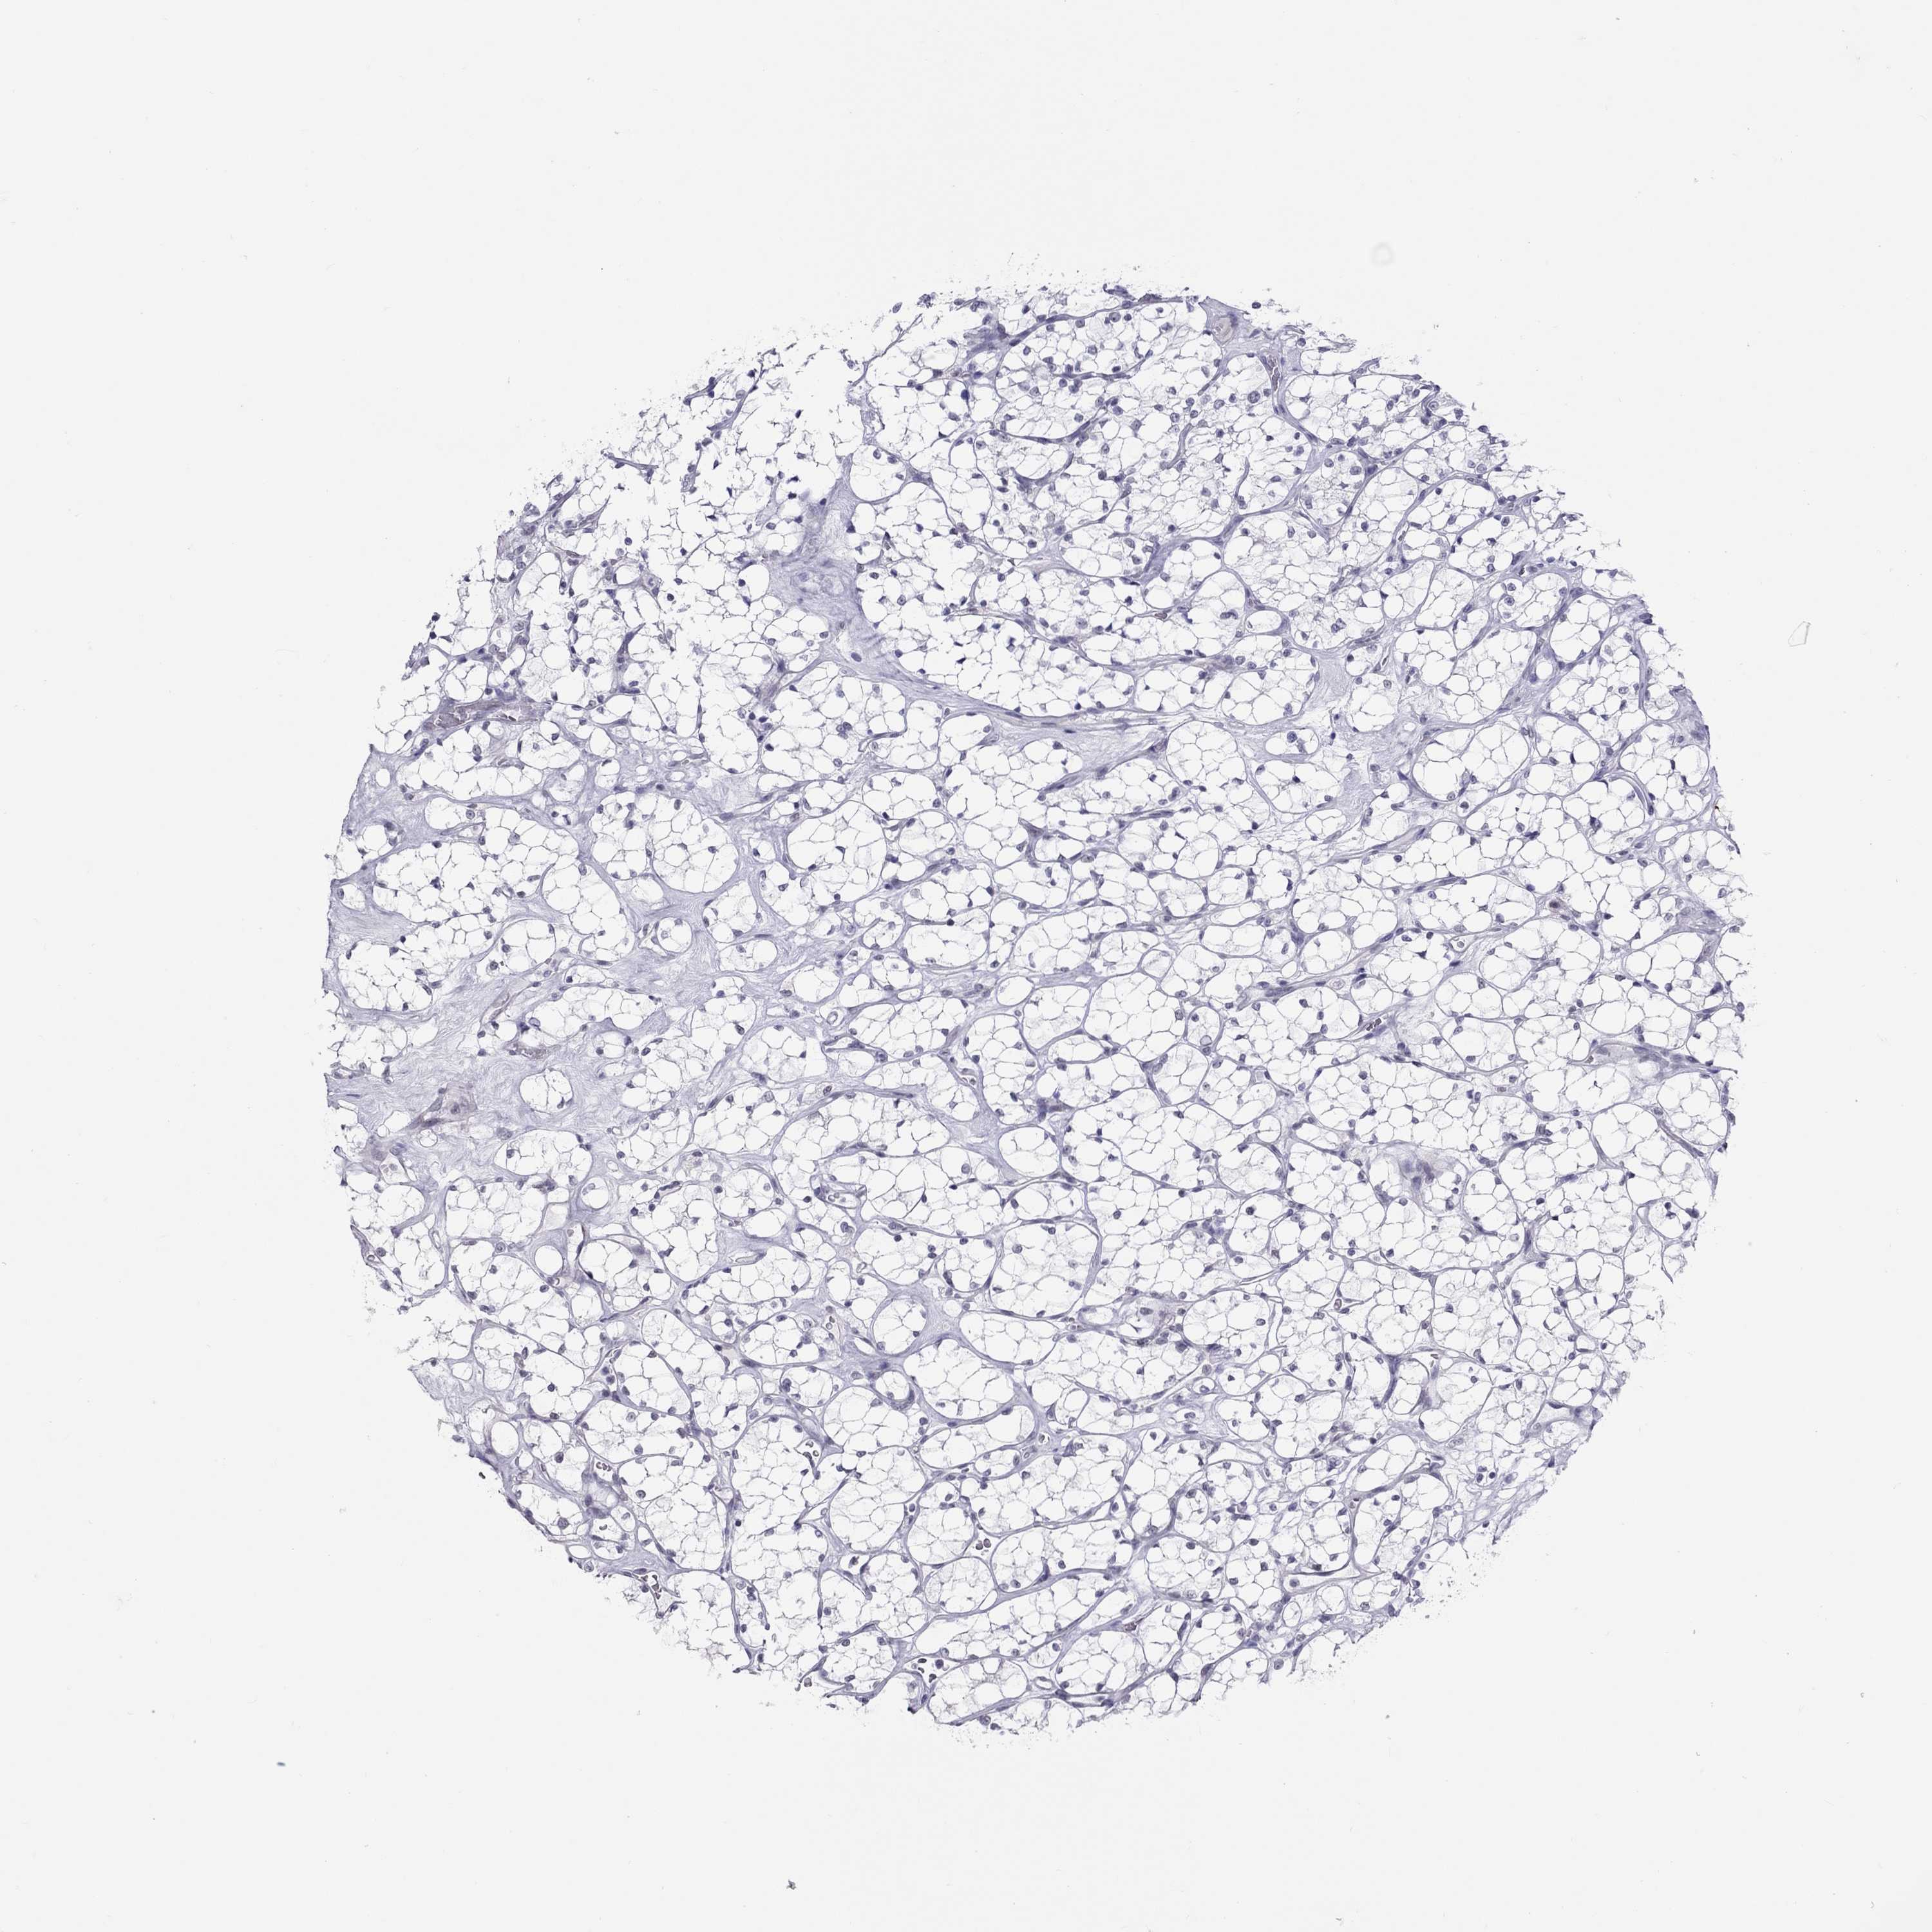

KICH TCGA KIRC TCGA KIRC VALIDATION KIRP TCGA PROTEIN RCC CPTAC PROTEIN EXPRESSION

Kidney chromophobe